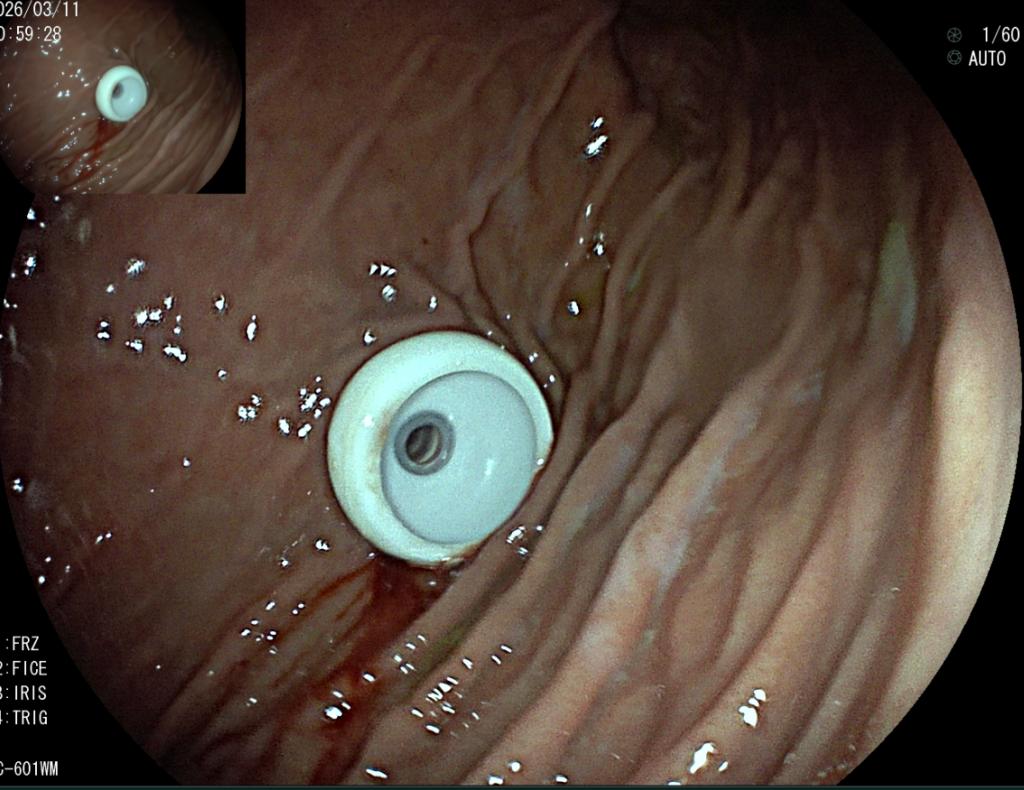

术前、术中、完成造瘘的食管

为破解这一临床难题,医院坚持守正创新,中西医并重。创新利用子镜直视探查+导丝精准引导+扩张+造瘘一体化的零射线术式。手术全程在高清直视下完成,术者能够清晰辨识狭窄通道与黏膜结构,安全引导导丝跨越闭塞段,同步完成食管扩张与经皮胃造瘘,三大技术无缝衔接,一次成型,全程零射线。创伤更小、恢复更快。

与传统术式相比,该技术实现了三大核心突破:一是全程零辐射,患者彻底免除电离辐射损伤,医护告别铅衣负重,更符合绿色微创理念;二是直视更精准,变“盲穿摸索”为“可视化操作”,显著降低穿孔、出血等并发症风险;三是一站式解决,一次手术同步打通进食通道、建立营养通路,快速改善患者营养状况与生活质量。